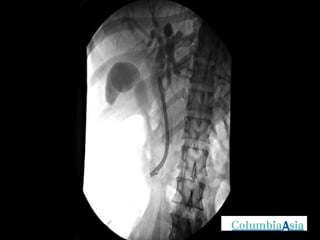

ERCP (Endoscopic Retrograde Cholangio Pancreatography) is an endoscopic procedure used to diagnose and treat issues in the bile and pancreatic ducts. It involves positioning an endoscope and using x-rays to view the ducts while performing procedures like draining bile ducts, removing gallstones, and placing stents. Potential complications include pancreatitis, bleeding, infection, or perforation. Careful pre- and post-procedure steps like monitoring and antibiotics are important to minimize risks.